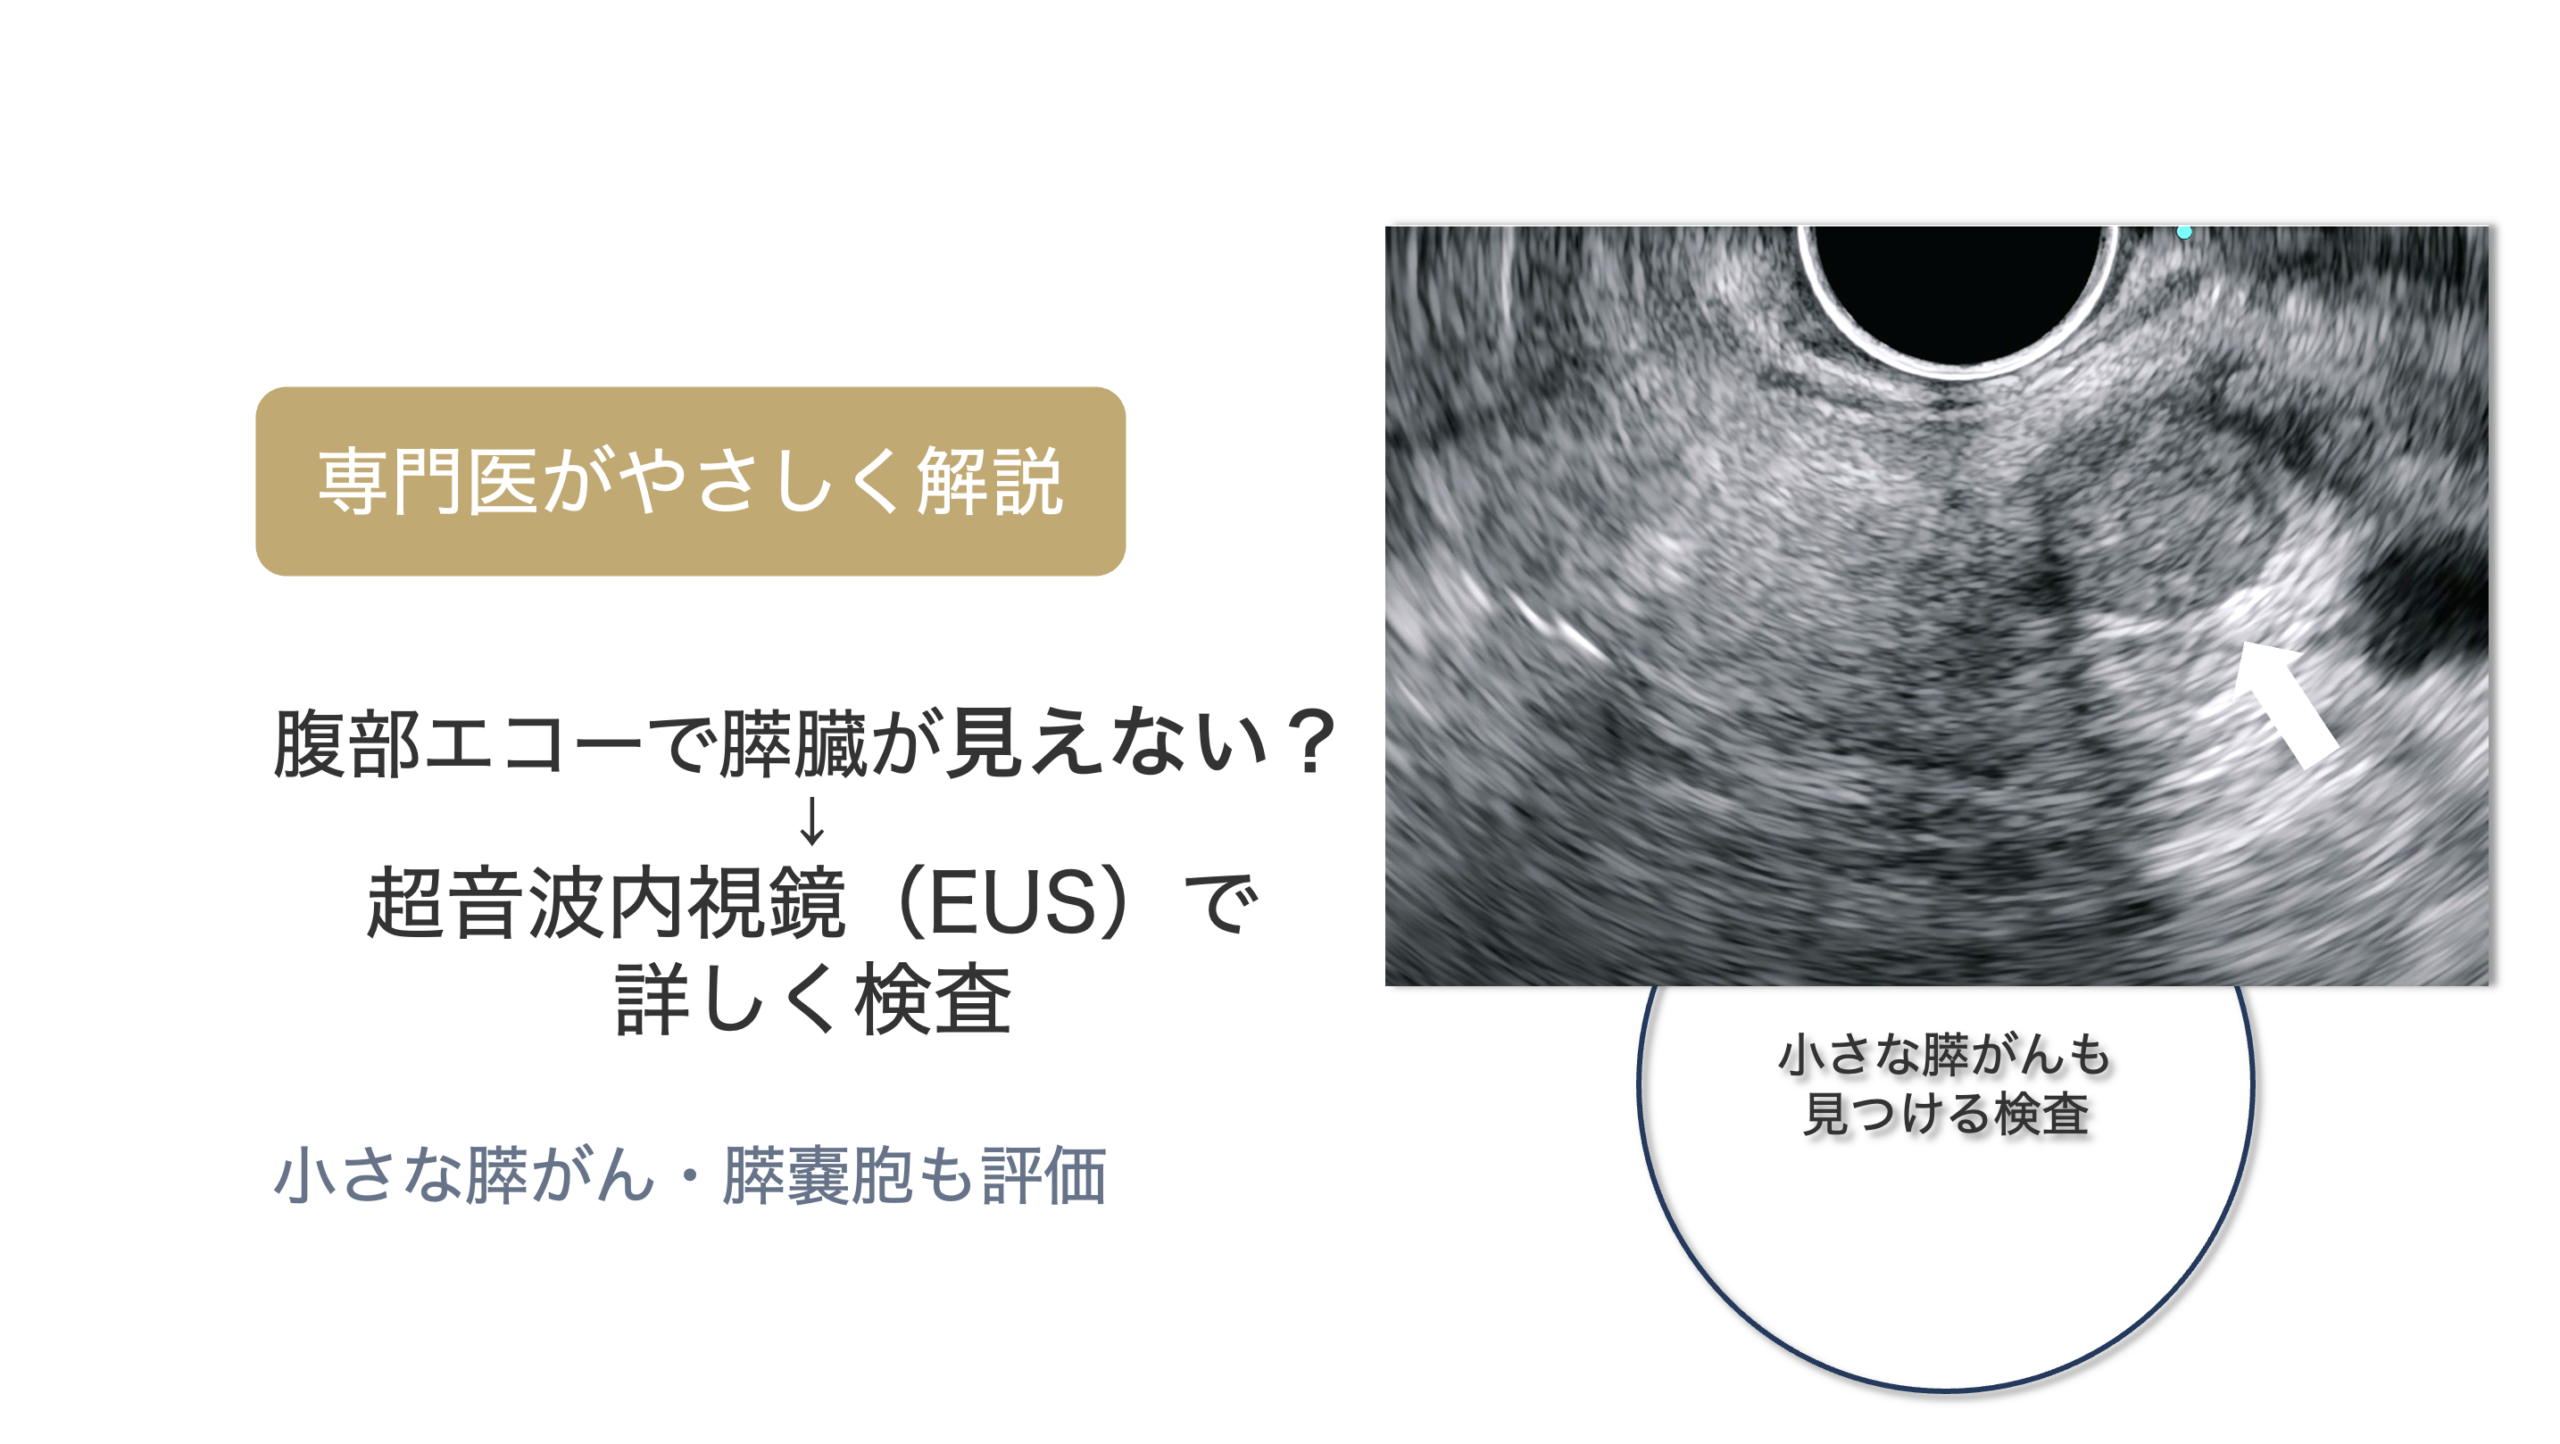

SPNの画像検査としては、腹部エコー、造影腹部CT、MRI、超音波内視鏡検査などがあります。

これらの画像で、SPNに特徴的な所見が認められれば、診断はそれほど難しくありません。SPNは画像検査で診断されます。

しかし画像所見だけではSPNの診断が難しい場合には、診断を確定するために本例のように超音波内視鏡下穿刺診が必要となります。

当院で施行した超音波内視鏡検査では、膵頭部に18X22mmの腫瘍を認め、内部には高エコー部(出血を反映)と低エコー部(嚢胞)が混在していました。

<超音波内視鏡>